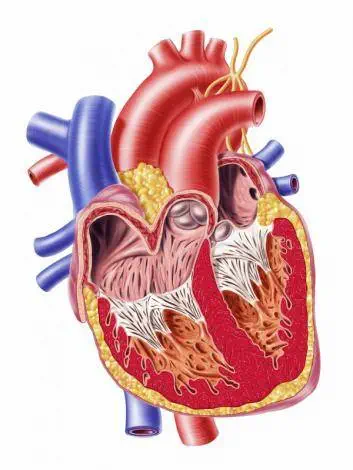

قلب دارای چهار دریچهی آئورت (aortic)، میترال (mitral)، ریوی (pulmonary) و دریچه سهلتی (س...

تعریف بیماری قلبی

بیماری قلبی، طیف وسیعی از شرایط را توصیف میکند که قلب شما را تحت تاثیر...